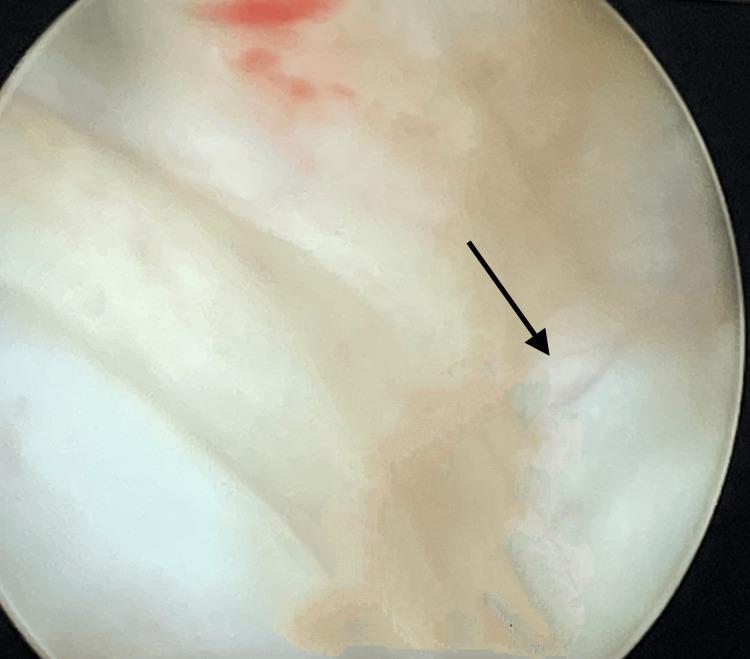

In many developing nations, vesicovaginal fistulas (VVF) continue to be a serious cause of concern. It leads to significant morbidity in urology for women. Patients of VVF experience social rejection as a result of constant dribbling, stink, and wetness, which degrades their quality of life. Hence, this report presents the case of a 45-year-old woman who approached the Outpatient Department of Obstetrics and Gynaecology with complaints of leakage of urine and urinary incontinence for three months with a surgical history of total abdominal hysterectomy. On per-speculum examination, leakage of urine was observed, and on per-vaginal speculum, a rent of 1×2 cm was palpable on the anterior wall of the vagina. For diagnostic assessment, cystoscopy and computed tomography urography confirmed the diagnosis of post-hysterectomy VVF. The surgical intervention involved cystotomy for the supratrigonal fistula, which was 1.5×1.5 cm in size, and the repair was performed by O'Connor's procedure. In conclusion, appropriate preoperative diagnosis, investigations, and principles of surgical intervention lead to improved surgical outcomes.

在许多发展中国家,膀胱阴道瘘(VVF)仍然是一个令人严重关切的问题。它导致女性泌尿外科出现显著的发病率。膀胱阴道瘘患者因持续滴尿、异味和潮湿而遭受社会排斥,这降低了她们的生活质量。因此,本报告介绍了一名45岁女性的病例,该女性因尿液渗漏和尿失禁三个月前来妇产科门诊就诊,有全腹子宫切除术的手术史。经阴道窥器检查时,观察到尿液渗漏,经阴道指诊时,在阴道前壁可触及一个1×2厘米的裂口。为进行诊断评估,膀胱镜检查和计算机断层扫描尿路造影确诊为子宫切除术后膀胱阴道瘘。手术干预包括对大小为1.5×1.5厘米的膀胱三角上瘘进行膀胱切开术,并采用奥康纳手术进行修复。总之,适当的术前诊断、检查和手术干预原则可改善手术效果。